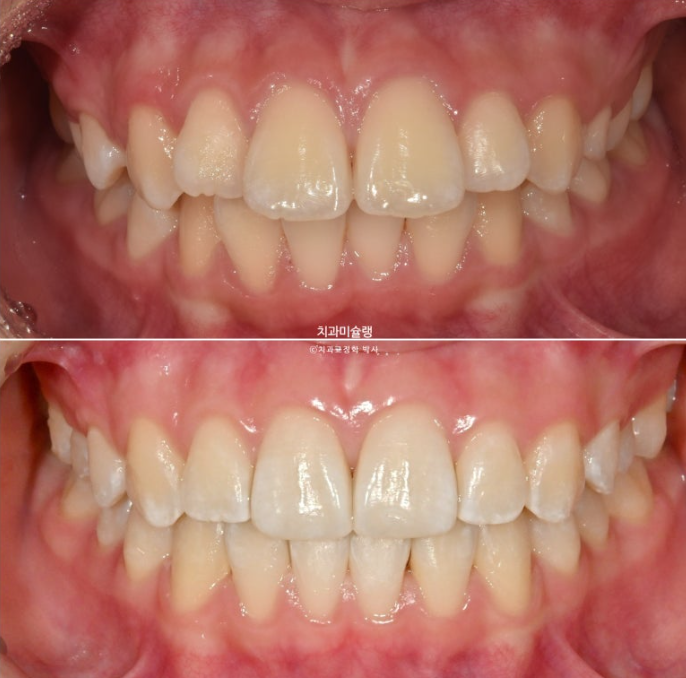

24.04

앞니가 유독 사이즈도 크고 아래로 내려와 있습니다.

측면에서 보면 뻗쳐서 튀어나와있죠

25.11

중심선은 잘 맞고 배열도 좋습니다.

그 사이 마지막 작은어금니까지 모든 영구치가 나와 교합이 완성이 되었습니다.

1급 물샐틈 없는 교합관계를 보입니다.

이제 전후 비교 보겠습니다.

24.04~25.11